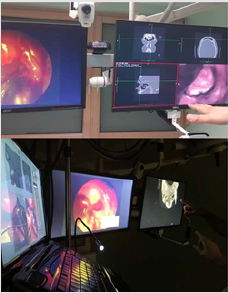

More specifically, for this research on shifting VR experience in our education/teleeducation and surgical/telesurgical [12,18] practice (as seen in Figures 1&2), we would need to equip VR laboratory and to develop different SW based AR scenarios that would enable above mentioned aims of creating the comprehensive and interdisciplinary environment in OR (IT in medicine) (Figure 3). Even more, in our future plans, MSCT and MRI datasets can be displayed in 3D using the AR/VR headset. The operating surgeon can move them, rotate them, and even move around them. Additionally, the surgeon can ‘enter’ the 3D models, and view the pathology from all angles based on touch-free surgeon’s commands which makes even the most delicate of rhinology structures tangible and visible in rich details [4], as already seen in the Stanford Neurosurgical Simulation and Virtual Reality Center.

Figure 3: Developing different SW based AR scenarios based on the exisiting medical datasets enhanced with virtual reality in order to enable comprehensive and interdisciplinary environment in OR.

c. With the development of VR lab/labs, we will collect high volumes of personal data, which will be stored in a maximum secured way, to make our own data collections and , and based on these data, we will improve further features of augmented and VR deliverables, which will be based on local surgeons’ needs and it will be international on the level of the joint VR lab (Figure 5).

d. Finally, we predict that such technology-oriented education and/or medical practice will impact the global labor market when offering next generation of highly-skilled IT and medical specialists/surgeons, including their cooperation as well as tele-assistance (as seen in Figure 6). By enabling this new approach, we aim to achieve a sustainable environment for developing skills that physicians/surgeons would need in their OR in the future; (e.g. “additive manufacturing of medical models” [38], CAS, NESS, and touch free surgeon’s commands- as “biomechanics” of the new era in personalized contactless hand-gesture, non-invasive surgeoncomputer interaction) as methods which exceed the contemporary educational and clinical limits.

Figure 5:Process of designing spatial anatomic elements, from both information technology and medical perspective. Using absolute value of hand position in the sensor coordinate system as a deflection of camera angles requires additional space and involves considerable amount of hand movements[2].

Figure 6: Application of virtual reality / augmented reality techniques in planning the surgery. The 3D-virtual reality and virtual endoscopy views could then be used uninterrupted and unburdened with unnecessary data when not required, independently of which application environment and settings were used2. Such dashboard could contain the most important functions and parameters concerning the current virtual reality10 or virtual endoscopy context[10].

h. Application of this new skills in medicine/OR, will show surgeons are as close as possible to real-life applications in medicine of the 21st century (such as robotic surgical procedures [37]), “by immersing themselves in 3D-views of their patients’ anatomy, doctors can more effectively plan surgical procedures” [4] (Figure 7).

Figure 7: Proposal of our VR and/or tele-VR lab for medical practice. For our team, this routine preoperative[38], as well as intraoperative procedure in our operation room, which enabled very precise and simple manipulation of virtual objects with the sense of physical presence at a virtual location[2,6], represents a more effective and safer endoscopic and virtual endoscopy procedure in our hands[10], in comparison with some ‘standard’ endo-techniques.